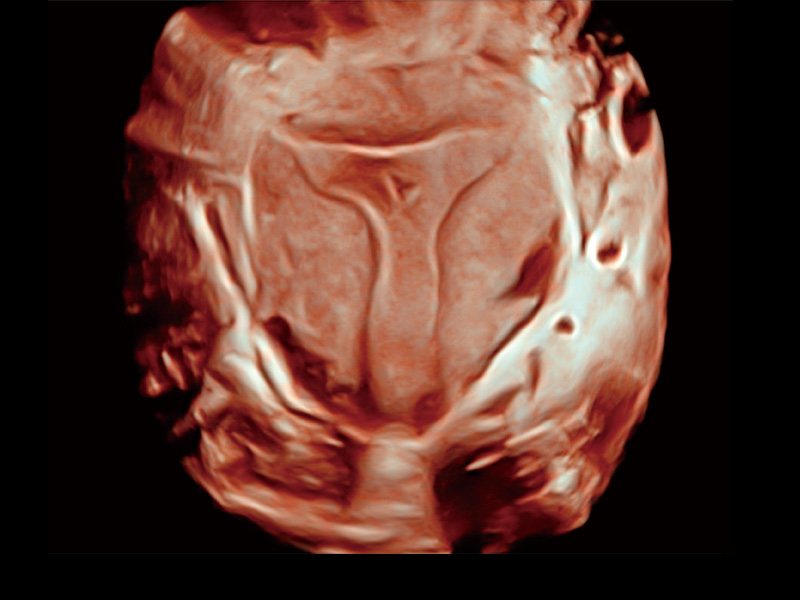

“生育问题”即关系民族复兴,也关系亿万家庭的幸福。随着婚育年龄推迟、社会压力增加等因素,越来越多人群也面临着“生不出、生不好”的问题。辅助生殖作为治疗不孕不育最有效的方法之一,也逐渐成为育儿新希望。而超声检查能为生殖需求人群的初诊评估提供宝贵的信息。 P20 Elite是球速体育入口匠心打造的一款生殖应用型彩超。她继承球速体育入口高端极光平台,突破性地将多款新型芯片及硬件模块进行整合,均衡了高端系统性能与小巧灵动机身。P20 Elite卓越的图像质量搭载专科探头,旨在为您提供全面的辅助生殖解决方案。

P20 Elite配备了丰富的生殖探头群和临床应用功能,在卵泡监测、穿刺取卵、胚胎移植、妊娠确认等领域,为生殖需求人群提供了新的临床机会,重新定义高端超声如何应用于生殖健康检查。